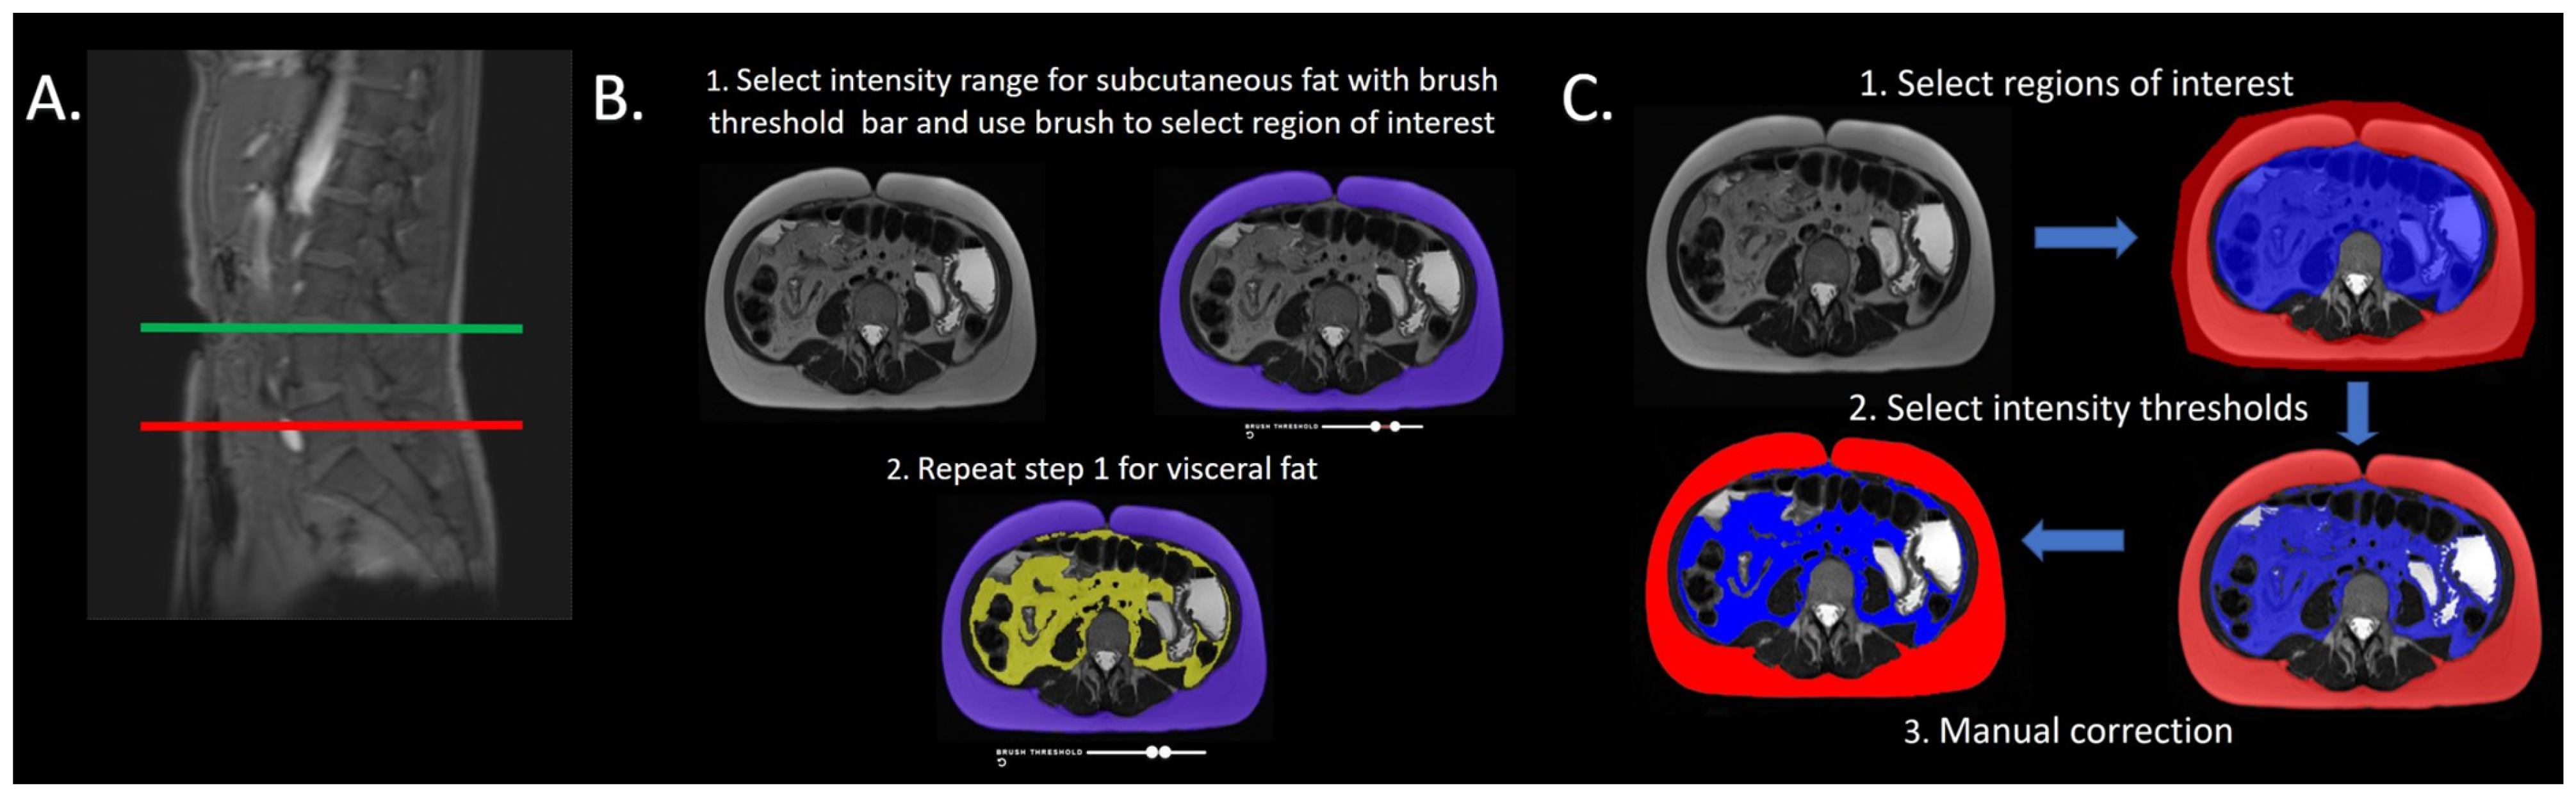

2.3. Platform 1 Image Analysis

2.4. Platform 2 Image Analysis